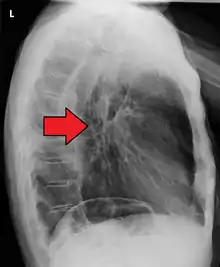

Esophageal cancer as shown by a filling defect during an upper GI series